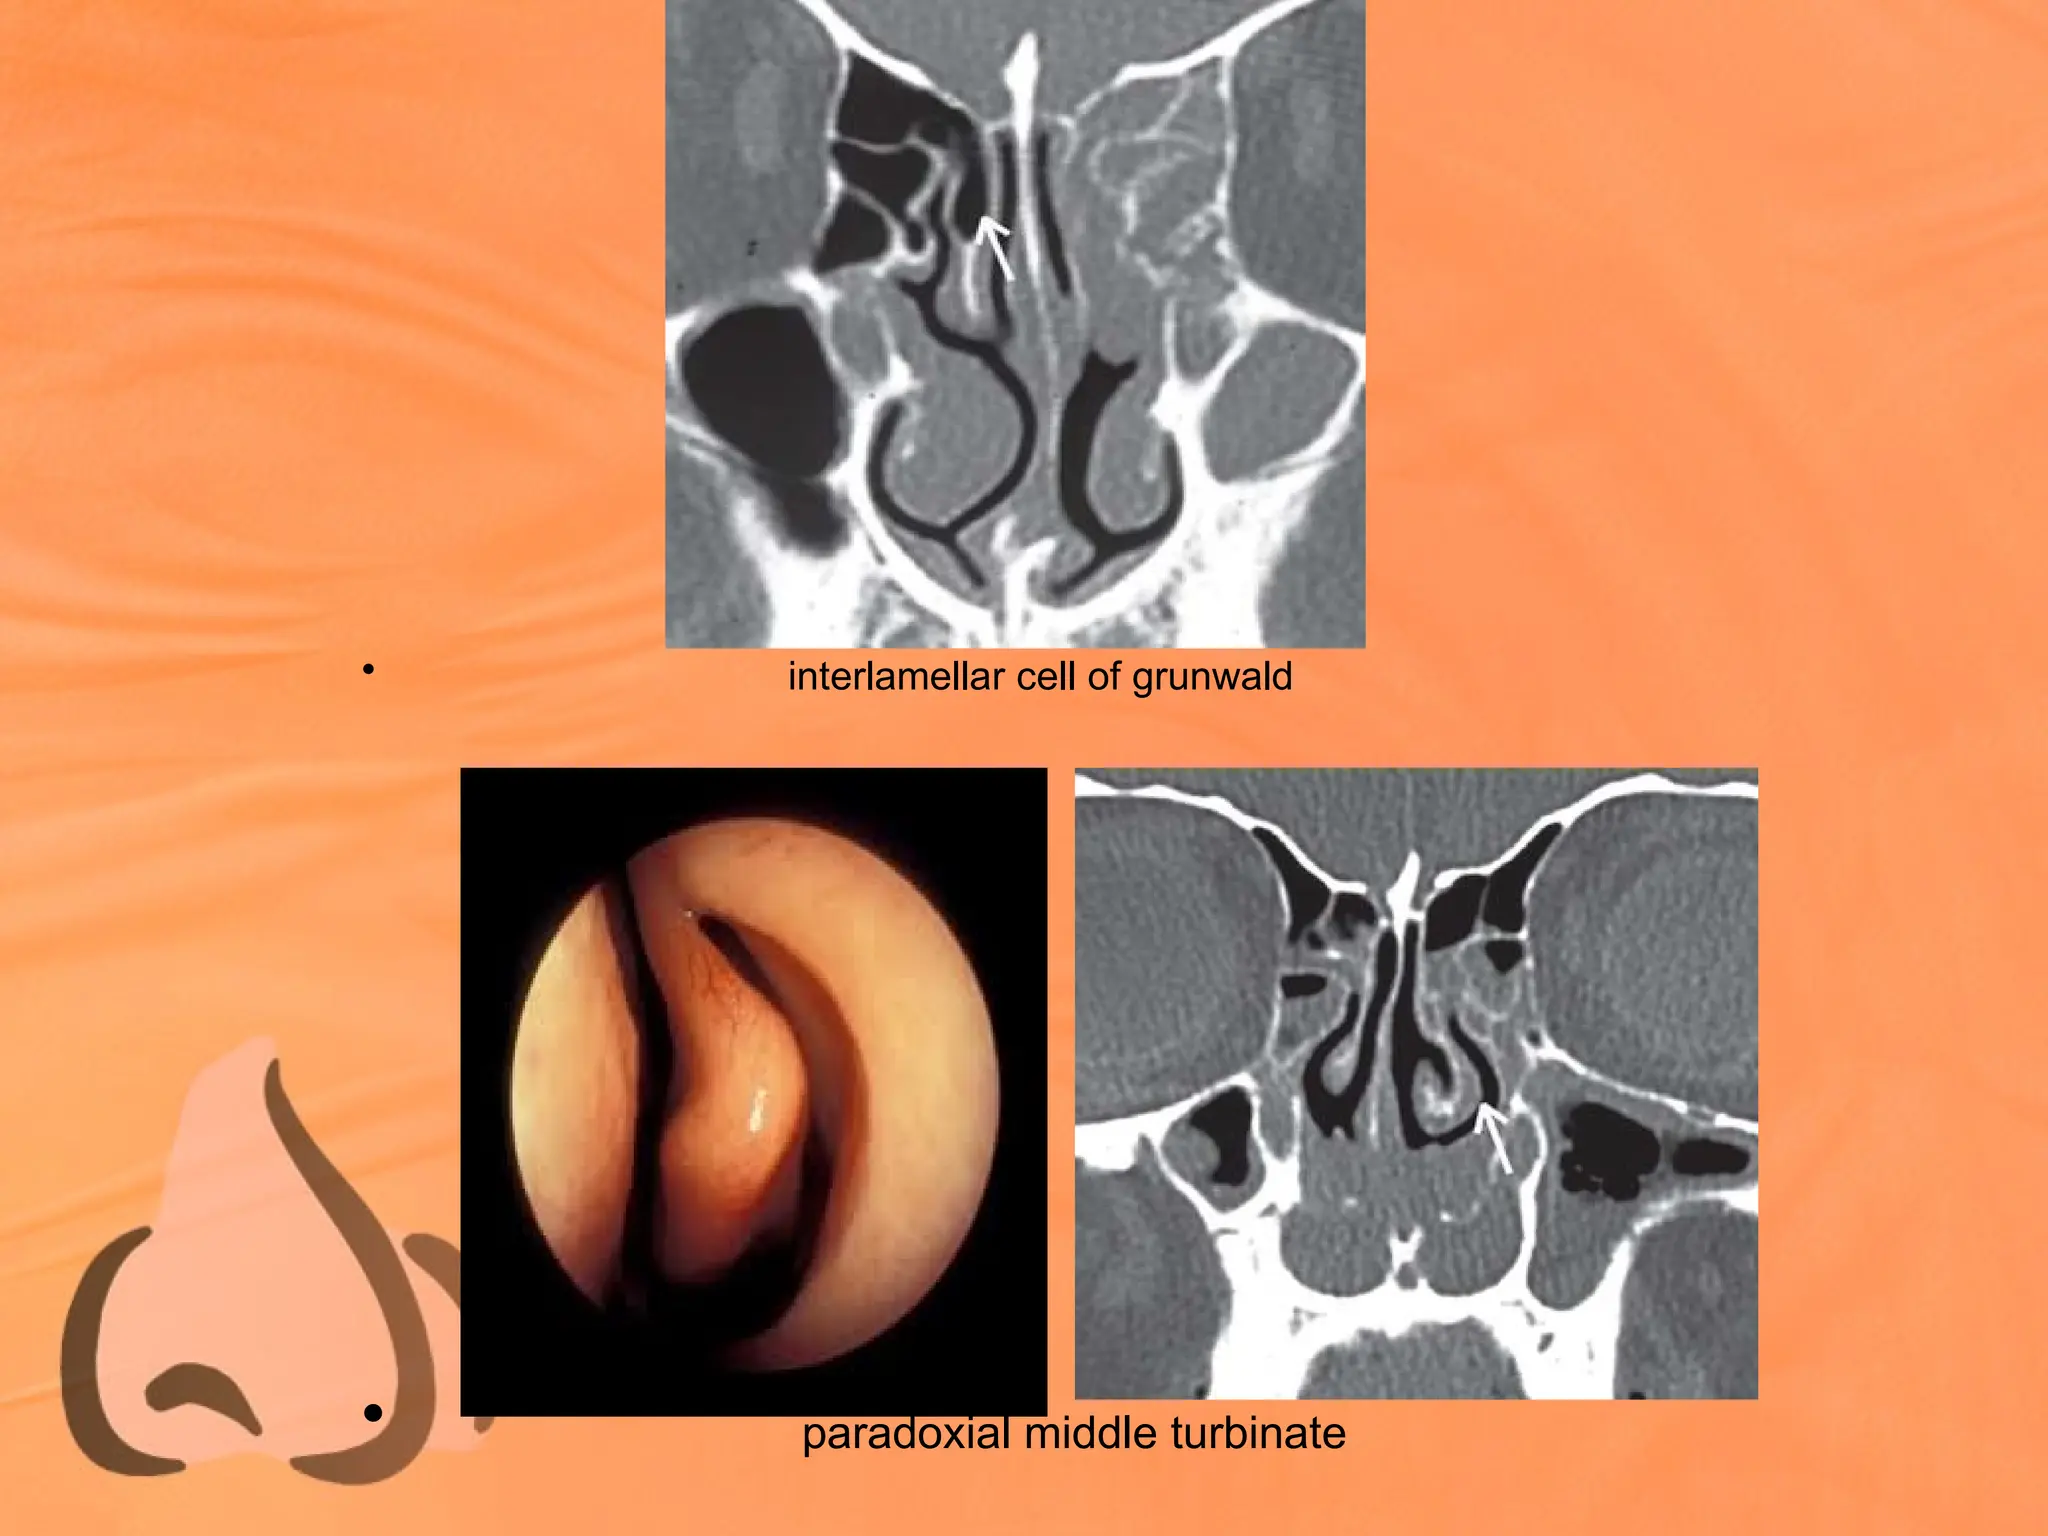

• May be pneumatized and ballooned up – Concha

• Occasionally Superior Meatus may pneumatize

vertical lamella of MT - Interlamellar cell of

Grunwald

smooth medial curvature - Paradoxically bent

Middle Turbinate

• interlamellar cell of grunwald

• paradoxial middle turbinate